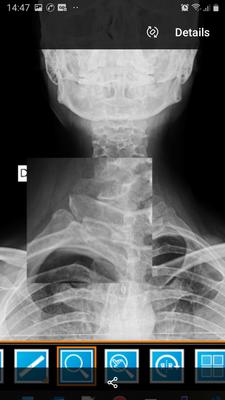

Posterior sternoclavicluar joint dislocations

I have a dislocated sternoclavicluar joint, a dislocated first rib at the intercostal joint.